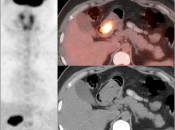

In general, we raise a suspicion of gastric malignancy if:

• Focal or regional hypermetabolic activity is accompanied by at least the suggestion of associated wall thickening (often difficult to assess if the patient’s stomach is suboptimally distended with water or oral contrast);

• Uptake is extremely focal (more likely to represent malignancy or ulcer);

• Focal/segmental uptake is extremely intense.

• Obviously, signs of associated metastatic disease on the scan give the radiologist much greater confidence in reporting a suspected primary gastric lesion.